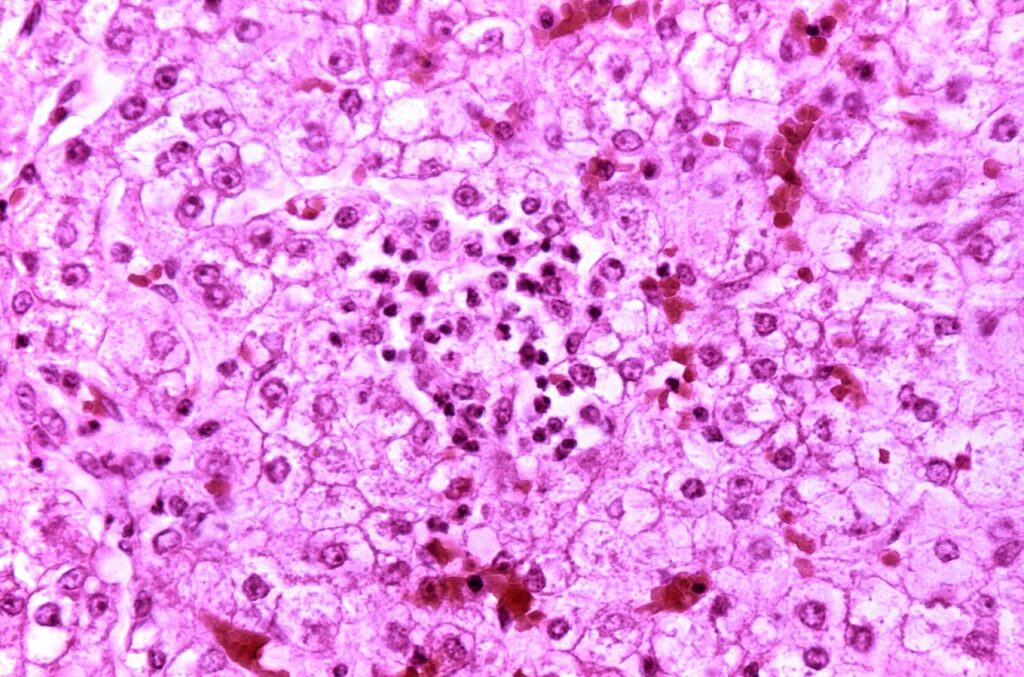

Reye syndrome is a rapidly worsening brain disease.[2] Symptoms of Reye syndrome may include vomiting, personality changes, confusion, seizures, and loss of consciousness.[1] While liver toxicity typically occurs in the syndrome, jaundice usually does not.[2] Death occurs in 20–40% of those affected with Reye syndrome, and about a third of those who survive are left with a significant degree of brain damage.[2][3]

The cause of Reye syndrome is unknown.[2] It usually begins shortly after recovery from a viral infection, such as influenza or chickenpox.[1] About 90% of cases in children are associated with aspirin (salicylate) use.[2] Inborn errors of metabolism are also a risk factor.[3] The syndrome is associated with changes on blood tests such as a high blood ammonia level, low blood sugar level, and prolonged prothrombin time.[2] Often, the liver is enlarged in those who have the syndrome.[2]

The serious symptoms of Reye syndrome appear to result from damage to cellular mitochondria,[14] at least in the liver, and there are a number of ways that aspirin could cause or exacerbate mitochondrial damage. A potential increased risk of developing Reye syndrome is one of the main reasons that aspirin has not been recommended for use in children and teenagers, the age group for which the risk of lasting serious effects is highest.[15]